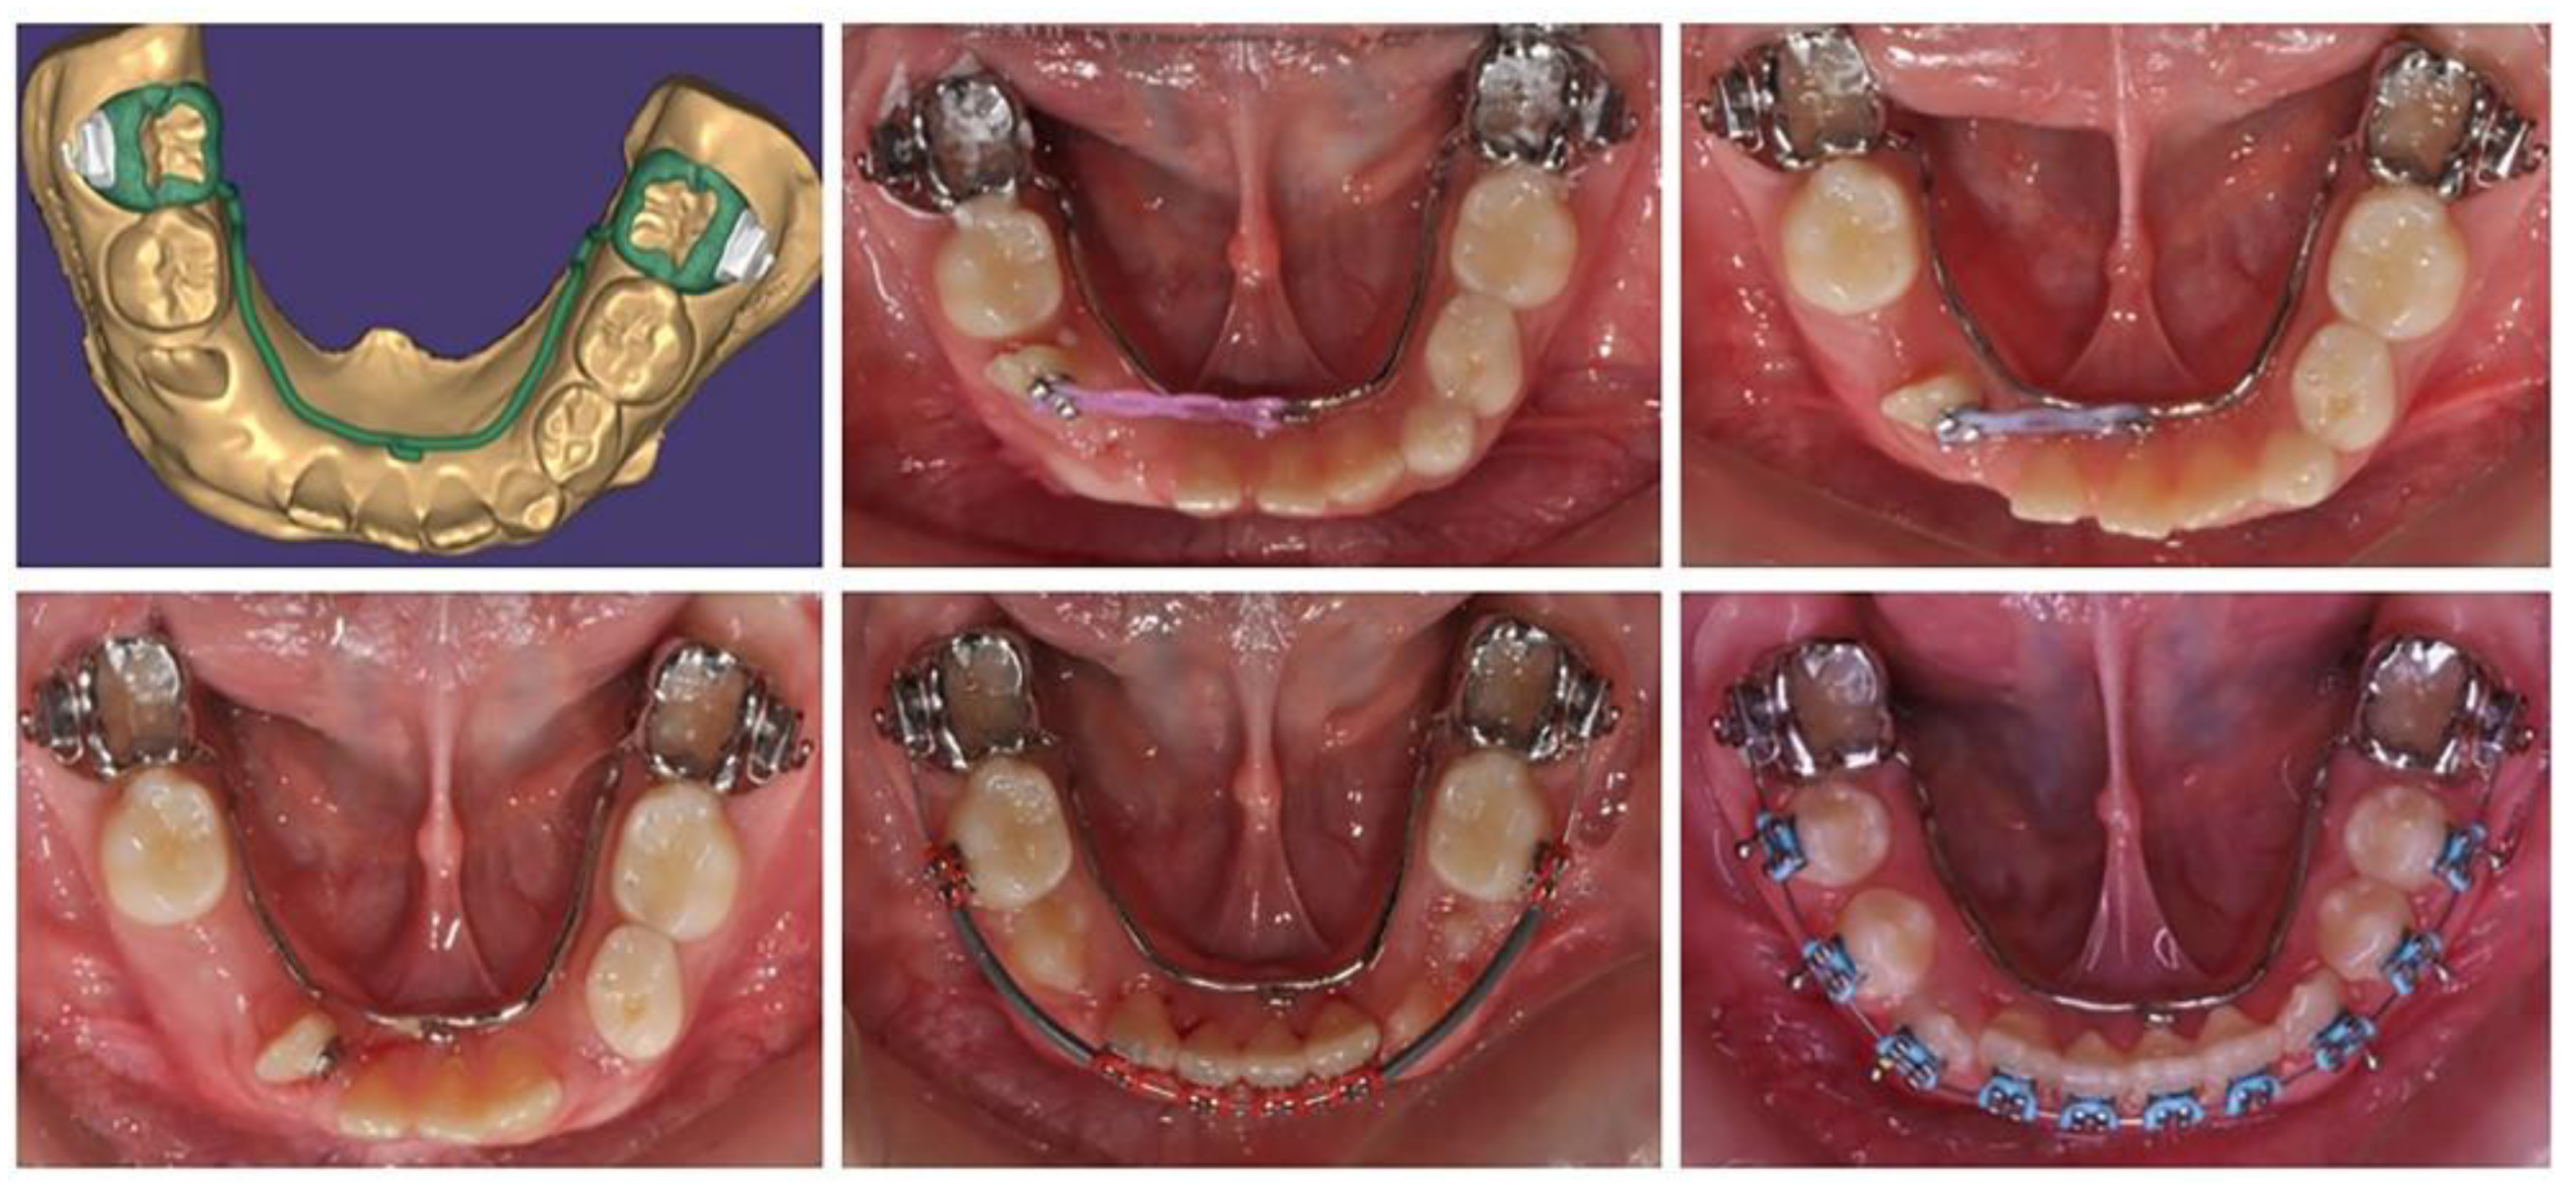

2.2.3. A 17-year-old female patient with a surgically repaired cleft of the hard palate. The patient's complaints are worsened aesthetics. During the first clinical examination, a reduced perimeter of the upper dental arch was found, crowding was observed both in the frontal and in the middle segment (in the area of premolars), the shape of the dental arch was changed - trapezoidal. The upper right lateral is located at the palate and the canine is medially located in contact with the central incisor. The upper frontal teeth are retruded and extruded, the bite is covered (Figure 6).

For the purposes of orthodontic treatment, extraction of two upper premolars (14 and 25) is required, which will provide a space exactly equal to the crowding size (the sizes of right lateral and left premolar). It is not desirable to design a biomechanical system in which there will be medial displacement of the distal anchorage teeth, as it occurs with the classic distal displacement of canines and anchorage second premolar and first molar (anchorage type A). In this clinical case, a stable distal anchorage zone is required, which can be provided by mini orthodontic implants or a rigid transpalatal arch involving all available anchorage teeth (Figure 7). When fabricating this type of digitally planned arch, elements can be incorporated into its design to aid in a more body movement of the canines, which will reduce the side-inclination effects of their movement.

The anchorage transpalatal arch construction, designed by us includes first and second molar rings, right second premolar lingual wall, first molar tube, and an extended right first molar hook for a higher level of applied canine distalizing force.

The teeth in the upper and lower dental arch are levelled and the occlusal relationships are normalized. The aesthetics of the frontal segment have been restored. From a smile with five frontal upper teeth (13, 11, 21, 12 and 13) a symmetrical smile was achieved with inclusion of the palatally located upper right lateral in a normal position. A well-designed metal anchorage system did not allow medialization of the abutment teeth. Complete preservation of the perimeter of the upper dental arch was achieved.

Figure 6. Initial status of patient with a surgically repaired cleft of the hard palate.

Figure 7. Transpalatal support arch with extension for distal movement of maxillary right canine - treatment progress.